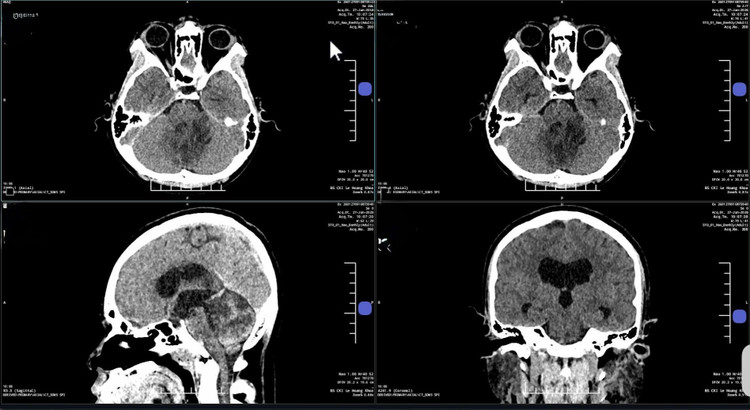

u-nao.jpg

Ảnh MRI 3 Tesla cho thấy khối u nằm sâu vùng góc hành não của bà Hạnh - Ảnh BVCC

Theo bác sĩ Sĩ, khối u chỉ cần chèn nhẹ một phần vùng hành não (nơi nằm sâu và nhạy cảm của não) cũng đủ gây liệt lưỡi, rối loạn nói, nuốt hoặc khiến người bệnh yếu liệt chi. Phẫu thuật vùng này đòi hỏi độ chính xác cao, chỉ cần lệch vài milimet có thể khiến người bệnh mất vĩnh viễn khả năng nói và nuốt.

Trước khi mổ, robot AI sử dụng công nghệ hòa hình đa lớp, tích hợp dữ liệu từ MRI và CT để tái tạo mô hình não 3D với độ phân giải cao. Nhờ đó, ê-kíp xác định rõ vị trí, kích thước cũng như mối liên quan giữa khối u và các dây thần kinh sọ 9, 10, 11, 12 cùng mạch máu nền sọ, lập kế hoạch tiếp cận tối ưu qua cửa sổ C1 - vùng nối giữa cổ và nền sọ.